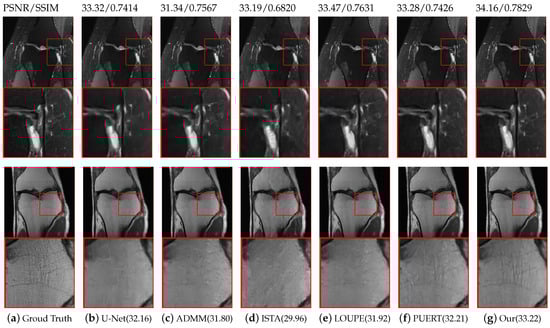

We compare the proposed reconstruction model with five representative state-of-the-art methods, namely U-Net [17], ADMM-Net [29], ISTA-Net [15], PUERT [22], and LOUPE [34]. The first three methods are reconstructed networks trained under a certain fixed sampling mask, while the latter two methods jointly optimize the learnable sampling mask and reconstruction network parameters. When performing comparative experiments, we used radial masks on the Brain and FastMRI datasets for tasks trained under fixed masks. Three learnable sampling masks enable both 1 D and 2 D sub-sampling optimization. Table 2 summarize the average PSNR/SSIM performance reconstruction at three CS ratios by various methods on the two datasets. It can be observed from the table that methods that use learnable sampling patterns generally produce higher PSNR than those with fixed masks, which confirms the superiority of the learned sampling mode.

Specifically, compared with the probability-based sampling mode optimization scheme employed by LOUPE and PUERT, it can be seen that at a sampling ratio of 5 % , the PSNR and SSIM of our model are significantly improved on both the Fast-MRI and Brain datasets. This is due to the fact that the data structure learned by our sampling mask is more pronounced at low sampling rates. On the Brain dataset, the gap between the proposed model and the results produced by PUERT   2 D and LOUPE   2 D narrows as the sampling ratio increases, which also shows that as previously mentioned, a 20 % sampling ratio can restore good results. On the Knee dataset, under three different sampling ratios, the proposed model performs slightly better than PUERT and LOUPE. In particular, at a sampling ratio of 5 % , the PSNR obtained is significantly increased by 0.77 compared with the PUERT results. This is because, with the large dataset, the sampling ratio is 20 % is still not enough for the Knee dataset. Under these circumstances, prior knowledge of the data structure is particularly important, while the masks we learn can help the reconstruction task. It can be observed from Table 2 that the use of neural networks enable five representative state-of-the-art methods to achieve real-time reconstruction speeds. As is shown in Figure 8, with a CS ratio of 10 % , the proposed model produces more reliable and clearer visual reconstructions than the other models in the comparison. In conclusion, the two experiments using two widely used MRI datasets indicate that the proposed model is superior to state-of-the-art methods in both quantitative indicators and visual quality.

Figure 8. Visual reconstruction comparisons with various state-of-the-art methods on the FastMRI [43] dataset with a CS ratio of 10%. Our model can recover more realistic details without producing overly smooth results.